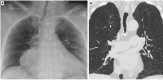

Fig. 3

On chest X-ray of the elderly, a common finding is the elevation of the left hemidiaphragm related to cardiothoracic surgery (A); on the contrary a lowering of the left hemidiaphragm due to increasing heart volume can be frequently seen as well (B). On sagittal MPR reconstruction, typings of the diaphragm caused by chronic obstructive pulmonary disease should not be misinterpreted as pathological findings (C)